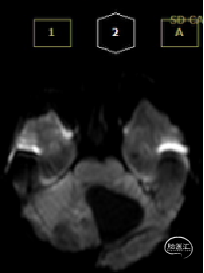

术前MRI